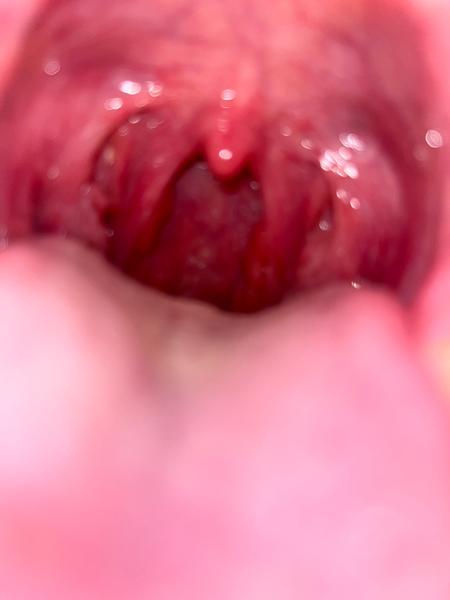

Ahojte, je podľa vás toto zapálene hrdlo? Už druhý deň ma škriabe, pobolieva ale prehĺtať viem zatiaľ normálne tak neviem čo by to mohli byt…

Podla mna je zapalene a dost.